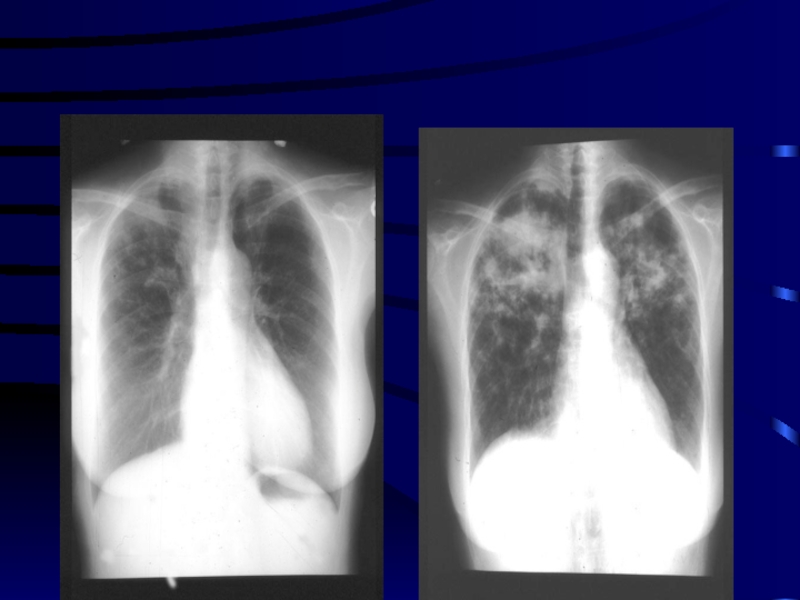

Слайд 72ДИССЕМИНИРОВАННЫЙ ТБ

ДИССЕМИНИРОВАННЫЙ ТБ 35–50 лет асоциальный контингент (бездомные) злоупотребление суррогатами алкоголясмерть за 1–6 дней

Слайд 732.3. Диссеминированный ТБ легких

Кортико-плевральная локализация

Симметричность поражений

Продуктивная тканевая реакция

Очковый

характер каверн

Хроническое течение

Развитие сетчатого и очагового пневмосклероза

Развитие

эмфиземы легких

Развитие легочного сердца

2.3. Диссеминированный ТБ легкихКортико-плевральная локализация Симметричность поражений Продуктивная тканевая реакция Очковый характер каверн Хроническое течение Развитие сетчатого

Слайд 74Диссеминированный ТБ легких

Диссеминированный ТБ легких